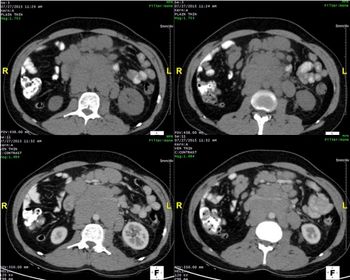

A 32-year old male presents with abdominal discomfort.